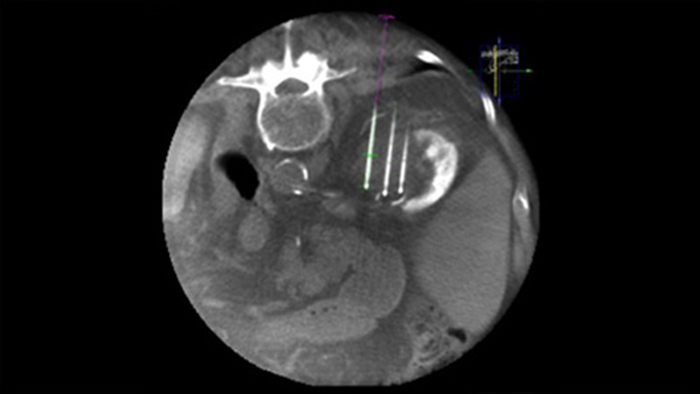

Dual View allows the overlay of a pre-procedure 3D image (CT/MR/PET-CT) on an intra-procedure 3D CBCT Dual to better visualisation the lesions and access critical input for needle planning.

XperGuide provides highly accurate live image guidance of each needle to a targeted position by overlaying pre-planned trajectories with fluoroscopic imaging.3